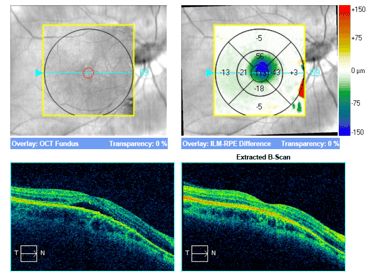

Przykłady PDT wykonanej z sukcesem u dwóch pacjentów ze zwiększona grubością naczyniówki.

Dwa przykłady nieskutecznej terapii fotodynamicznej w przebiegu CSCR. Zwraca uwagę brak pogrubienia naczyniówki u tych pacjentów.